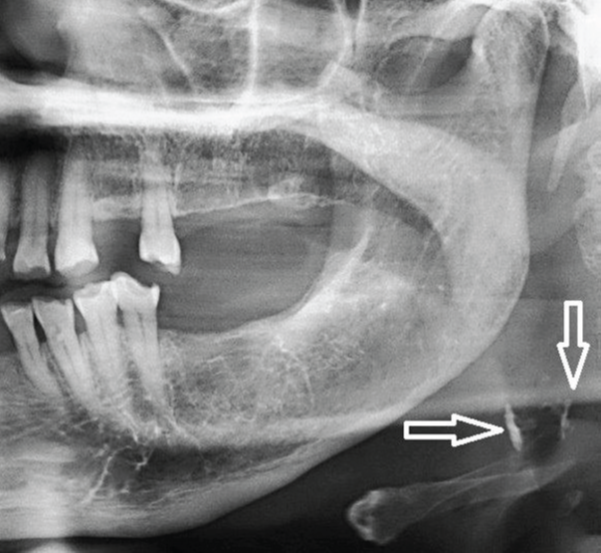

2) Identify the multiple asymptomatic radiopacities below the lower border of mandible. Patient was 45 years old and suffered from Tuberculosis in the past.